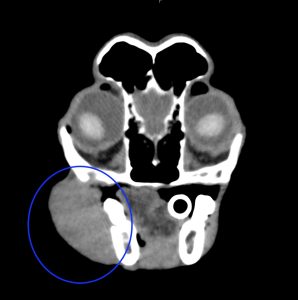

今回治療させていただいたワンちゃんは、口の奥に出来物が見つかったとのことで来院され、頬粘膜〜下顎の歯肉腫瘤を生検したところ、メラノーマと診断されました。

腫瘍の増殖スピードが速く、日に日に大きくなっていき、このままでは食べられなくなる可能性がありました。

手術は、腫瘍に片側下顎骨の大部分をつけて切除しました。また、下顎リンパ節、内側咽頭後リンパ節も切除しました。病理検査では、腫瘍は取り切れており、リンパ節転移もなしとの結果でした。